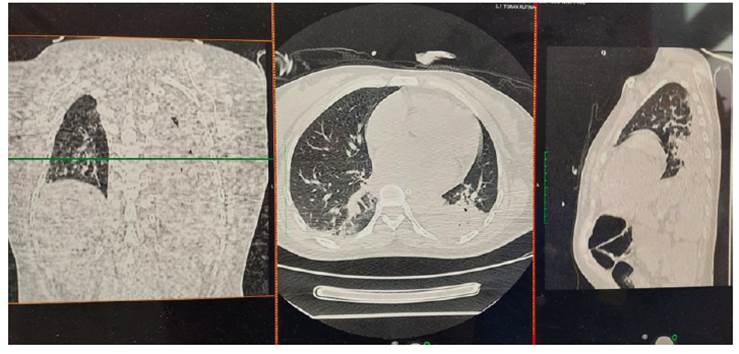

Brain multislice spiral tomography (MST) with coronal and sagittal reconstructions (Figure 1) showed extensive right cerebral infarction (in the middle cerebral artery (MCA) and the anterior cerebral artery (ACA) territory, with a large mass effect, conditioning deviation of the midline by 14 mm to the left and partial collapse of the supratentorial ventricles. Increase density of the MCA was evidenced, probably related to thrombus (Alberta Stroke Program Early CT Score (ASPECTS):0). Chest MST with coronal and sagittal reconstructions showed typical signs of Covid-19 ("ground glass", vascular thickening, cobblestone pattern, parenchymal bands and bilateral consolidations predominantly left). CORADS: 513.

Figure 2 Case 1. Non-contrast chest tomography (with coronal and sagittal reconstruction) shows typical signs of Covid-19 - ‘ground glass’, vascular thickening, cobblestone pattern, parenchymal bands and bilateral consolidations, predominantly left. CO-RADS: 513.